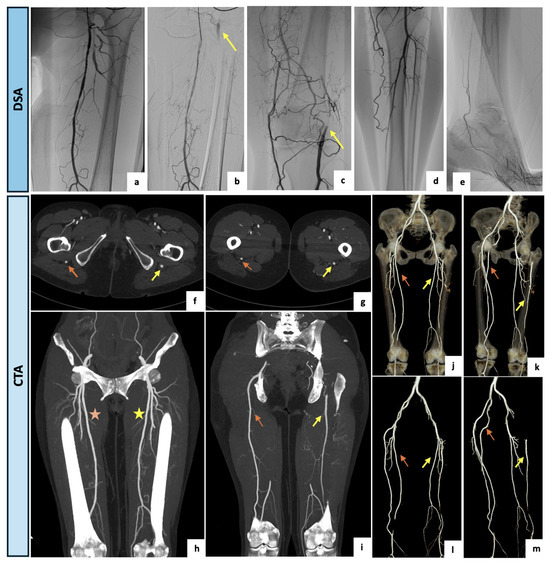

2.4. Case 4

A 61-year-old woman was referred to the outpatient clinic of the Vascular Surgery Department for a type IIb bilateral claudication of her lower extremities with a recent worsening on the left side. The patient had a clinical history of active cigarette smoking, arterial hypertension, type 2 diabetes and moderate-to-severe renal impairment (eGFR of 29.9 mL/min/1.73 m2). Right peripheral pulses were present whereas on the left side the femoral pulse was diminished, and distal pulses were not palpable. Perfusion, sensation and motor function were bilaterally maintained. The arterial DUS of the lower limbs showed a complete occlusion of the left SFA at the Hunter’s canal with a restoration of blood flow at the level of the articular tract of the popliteal artery, where a monophasic and low peak systolic velocity flow was detected. On the right lower limb, physiological popliteal and tibial flow were assessed. After a multidisciplinary discussion of the clinical case, a primary angiographic approach with attempted left SFA revascularization was indicated with the aim of reducing the contrast medium burden. After an adequate periprocedural hydration protocol and under local anesthesia, a left antegrade common femoral access was obtained. The preliminary selective digital subtraction angiography showed a hypoplasic and interrupted left SFA, lacking the usual continuation. The popliteal artery was instead supplied by collateral pathways originating from distal small branches of the SFA and the deep femoral axis. Surprisingly, an arterial vessel suggestive of incomplete PSA was retrograde perfused via deep femoral collateral pathways and visualized both proximally and distally as brief tracts. Due to the incidental finding of the PSA, the case was rediscussed, and CTA was accordingly indicated. Upon CTA examination (Figure 5), a bilateral PSA was found. On the left side, a type 2A PSA with a proximal focal occlusion and re-habitation via gluteal collateral pathways, as well as a distal femoral significant stenosis, were detected. The right lower limb presented a type 1 complete PSA. The patient was thus submitted to a medical management program consisting of smoking cessation, exercise training, glucose-lowering therapy, anti-platelet agents and cilostazol, with an initial slight improvement of symptoms. Since the PSA assumed a dominant role as the main blood supplier to the left lower limb, the patient qualifies as a candidate for endovascular recanalization with PSA angioplasty if symptoms worsen or persist.

Figure 5.

(a–e) Intraprocedural selective angiographic images obtained after a left antegrade common femoral access. (a–e) The angiograms demonstrate a diffusely hypoplasic and interrupted left SFA, lacking the usual continuation, and a popliteal artery supplied by collateral pathways originating from the distal small branches of the SFA and the deep femoral axis. (b,c) Surprisingly, an arterial vessel suggestive of incomplete PSA was retrograde perfused via deep femoral collateral pathways and visualized both proximally and distally as brief tracts (yellow arrows). (f–i) Axial and coronal maximal intensity projection views of the CTA confirming a bilateral PSA. On the left side, a type 2A PSA (yellow arrows) and a distal significant stenosis of the SFA (yellow asterisk) were detected. The right lower limb presented a type 1 complete PSA (orange arrow) along with a regular SFA (orange asterisk). (j–m) Three-dimensional reconstructions with and without bone structures. On the left side, a type 2a PSA with a proximal focal occlusion and re-habitation via gluteal collateral pathways, and a distal femoral significant stenosis was detected (yellow arrows). The right lower limb presented a type 1 complete PSA (orange arrows).